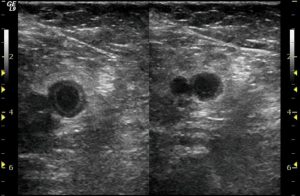

The most common test to diagnose deep vein thrombosis is ultrasound. A DVT ultrasound protocol involves scanning throughout the limb. There are three signs of deep vein thrombosis on ultrasound: lack of compressibility, lack of color flow and direct visualization of clot. Of the three, the most accurate is the inability to compress the vein: